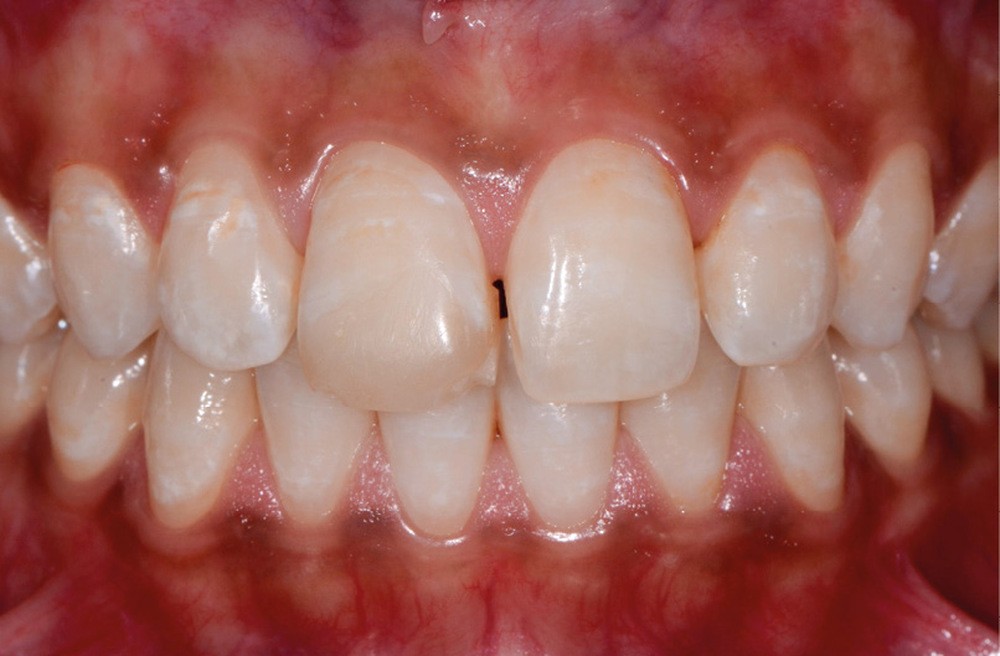

Les dyschromies extrinsèques

Elles sont causées par des agents colorants externes qui se déposent généralement sur la surface amélaire. Leurs origines sont diverses : alimentation (fig. 1b), tabac (fig. 1c), plaque bactérienne ou bactéries chromogènes (fig. 1d), ainsi que certains médicaments. La réalisation d’un aéropolissage en complément du détartrage initial est généralement suffisante pour éliminer efficacement ces colorations. Cependant, le patient doit être prévenu qu’en l’absence de modification de ses habitudes de vie, celles-ci reviendront [2, 4].